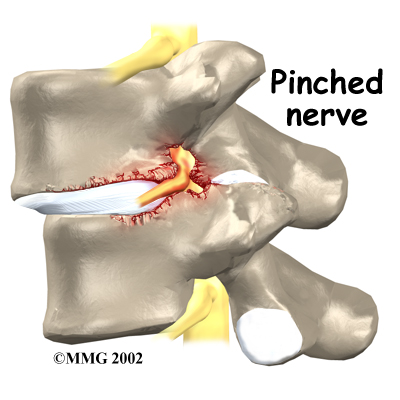

The spinal nerves are also affected by too much vertebral motion. They begin to rub where they pass through the neural foramina and become swollen and irritated. Also, the neural foramina narrow when a vertebra slides too far forward or backward over the vertebra below. This immediately where they pass through the neural foramina. Nerve swelling, irritation, and pinching produce neurogenic pain. This type of pain often radiates down one or both legs below the knee. Fusion stops this harm to the nerves.